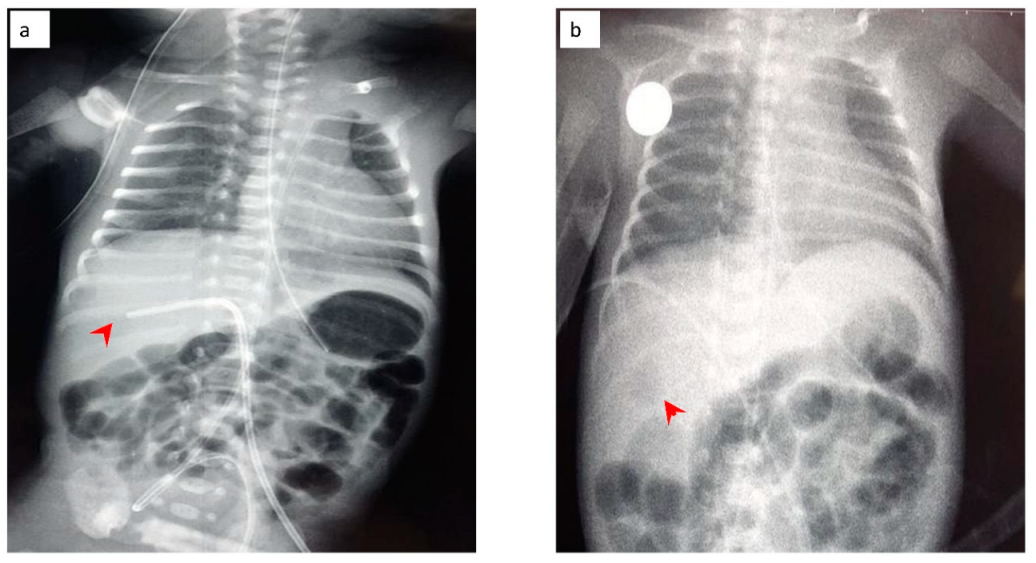

Figure 3.

Radiography of the neonate on the day of deterioration. Non-specific signal characteristics in the abdomen, such as distention and poor distribution of bowel gas. A clavicular fracture clavicle is noted on the right (red arrowhead).

The neonate was then stabilized, and ultrasonography was performed in order to differentiate the possible causes of blood loss. No IVH was confirmed by cranial ultrasonography, while abdominal ultrasonography depicted a hypoechogenic intrahepatic irregular lesion on the right lobe (3.4 cm × 1 cm) (Figure 8a), with hematoma being the possible diagnosis from the radiologist. Chest and abdominal radiography (Figure 9a) showed an abnormal position of UVC, so it was removed. On the following radiography (Figure 9b) air in the branches of right portal vein and hepatic parenchyma was noted (as shown in Figure 9b).

Figure 9.

(a) Chest and abdominal radiography depicting the abnormal position of umbilical venous catheter in the liver (red arrowhead); and (b) chest and abdominal radiography depicting air in the branches of right portal vein and hepatic parenchyma (red arrowhead).